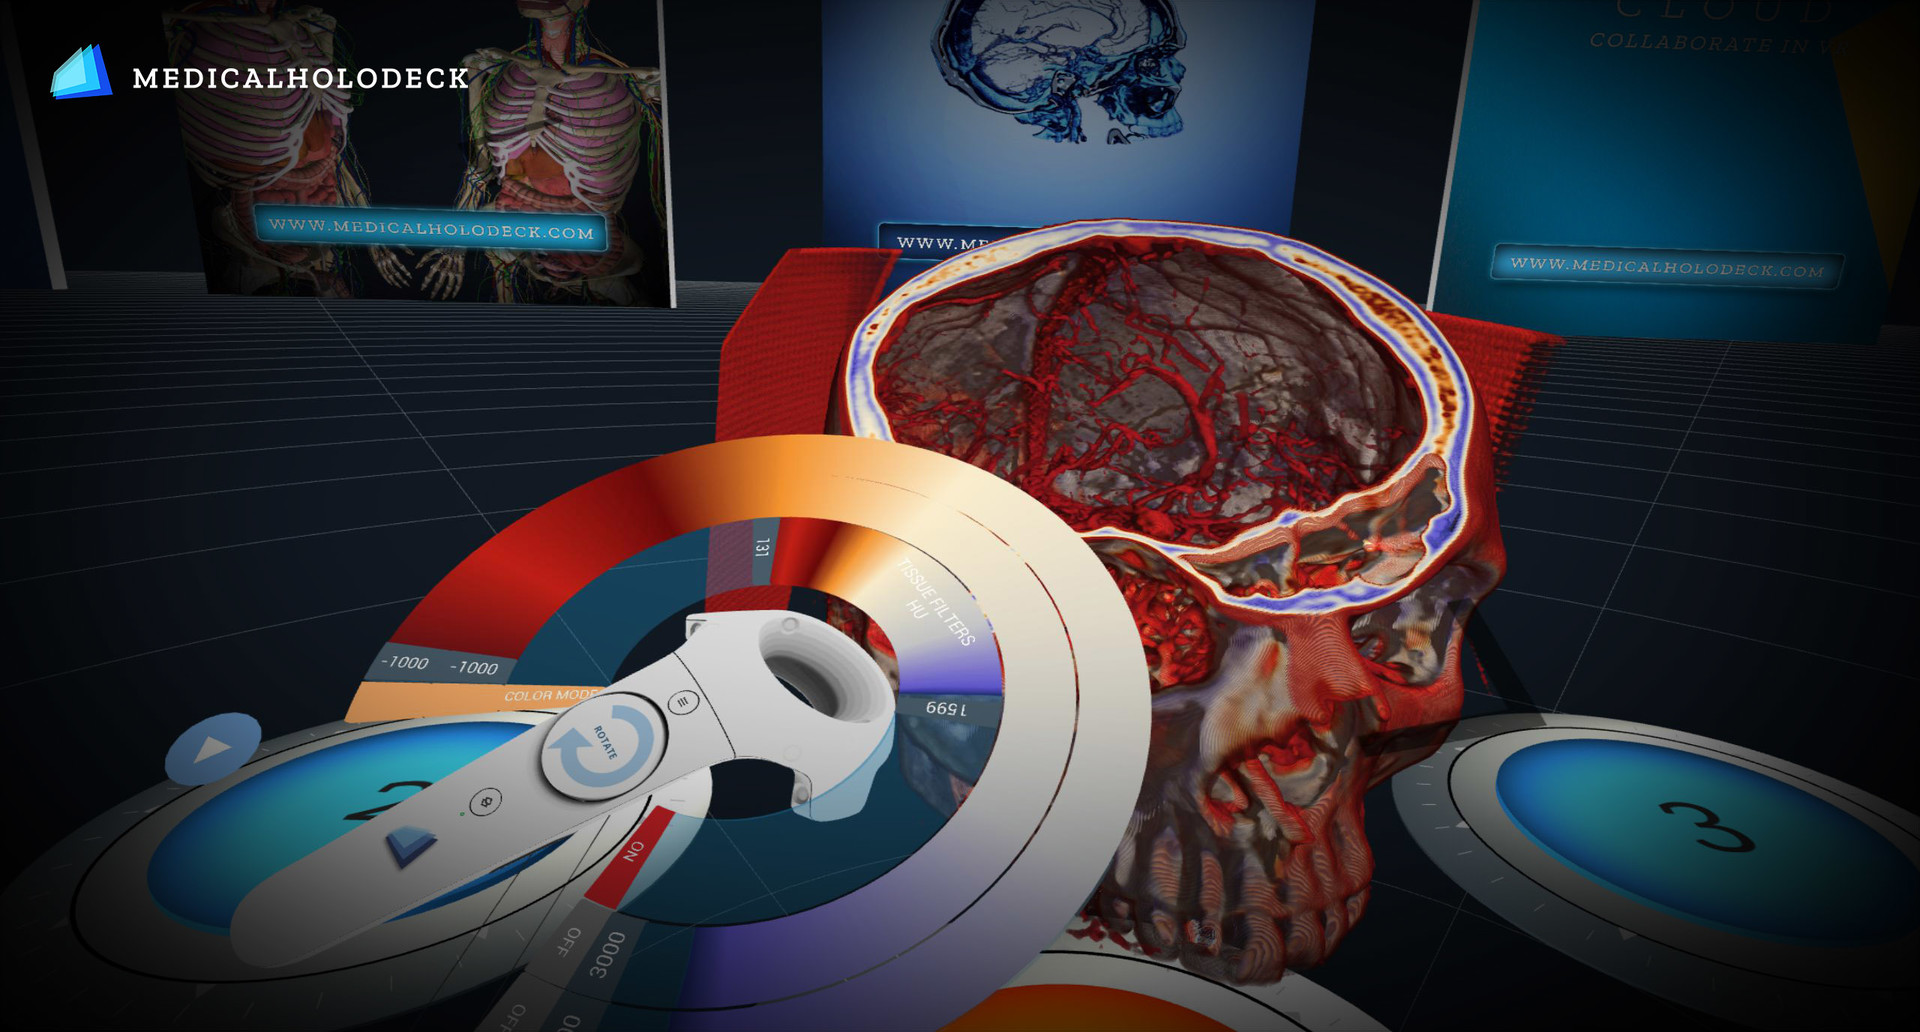

Work and collaborate on 3D medical Data in real 3D Virtual Space: Medicalholodeck is the medical Platform for Virtual Reality. Surgeons use it to prepare their upcoming surgeries, professors to teach human anatomy and radiology, students to study human anatomy, medical imaging and bio visualization Labs to work on 3-dimensional scientific data.

Surgery preparation in virtual space: Prepare upcoming surgeries in the most efficient and immersive way possible. Connect groups of users in Medicalholodeck, load DICOM data from your patients within seconds, and collaborate, work and discuss together medical cases in a real 3D virtual space.

Virtual Reality Anatomy Dissection Table